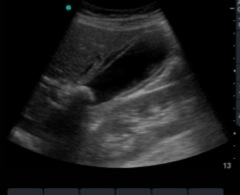

nl galbladder

Acute cholecystitis

Gallstones